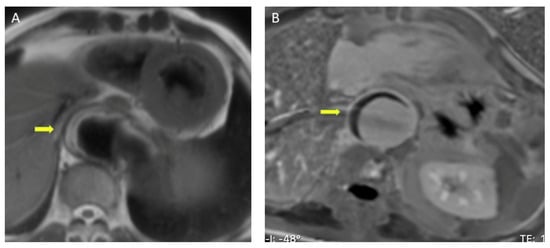

Figure 3.

Intramural hematoma on CT using (A) non-contrast CT and (B) CT angiography: crescentic, high-attenuating regions of eccentrically thickened aortic wall on non-contrast CT (arrow). A diffuse pericardial effusion (*) was also visible in both scans. (C) Penetrating ulcer on CT: CT angiography image showing a penetrating ulcer of the descending aorta as a contrast-filled, out-pouching into the thickened aortic wall (arrow). CT, computed tomography.